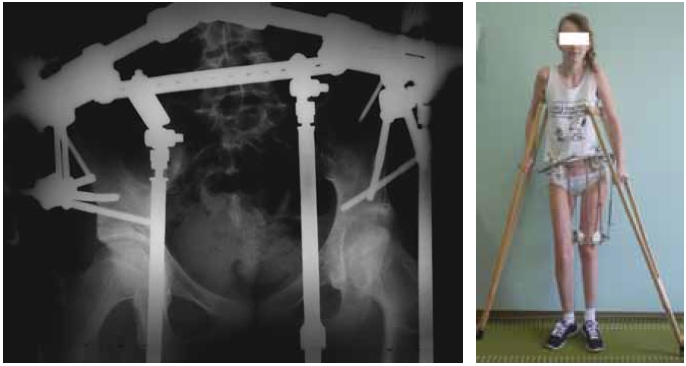

Radiography and computed tomography of the hip joints (Fig. 2) showed that on the left, the femoral head was deformed and had an irregular shape and uneven contour. The contour of the acetabulum was uneven. The joint gap was sharply narrowed and was not traced in some places. The diagnosis was a consequence of septic coxitis, secondary deforming coxatrosis on the left, and fibrous ankylosis of the left hip joint. Considering the clinical and radiological picture, the pronounced vicious position of the lower limb, the absence of pain syndrome, and early adolescence, we decided to conduct a stepwise organ-preserving complex treatment aimed at eliminating the vicious position of the limb by eliminating the fibrous block between the articular surfaces with subsequent development of movements in the hip joint. The treatment plan included a combination of the following modern methods: distraction in the device, arthroscopy, intra-articular injections, therapeutic exercises and other rehabilitation measures. The first stage (Fig. 3) for the expansion of the joint space involved the imposition of a wire-rod distraction apparatus of the MKC on the pelvic bone and the left hip with spinal adductomy.

Fig. 3. Radiography image and patient appearance after the first stage of treatment. The distraction wire and rod apparatus is placed on the pelvis and the left hip; due to the distraction, the joint space of the left hip joint is stretched to 1.5 cm. The patient is activated in the apparatus